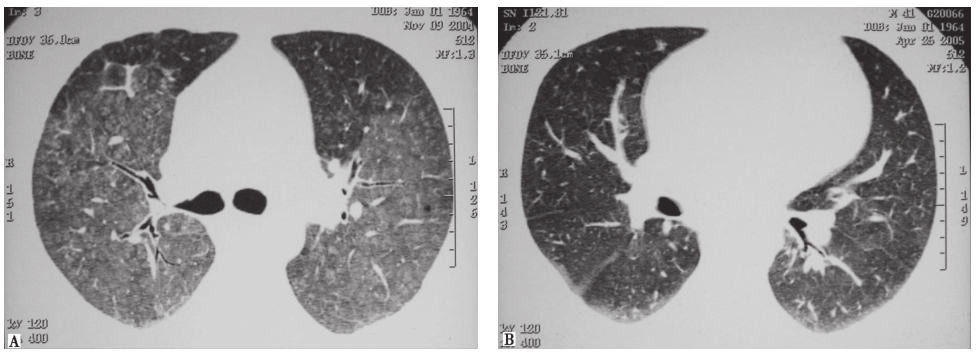

胸部CT(发病第14天):左肺下叶高密度影,边界欠清晰,其间可见多发囊性病变(图2)。

图2 发病第14天胸部CT表现

胸部CT:左肺下叶病灶边界较为清楚,表现为实变、空洞,空腔病灶内有液平(图13),其脓液界面呈类蜂窝状气囊影改变。

图13 入院后胸部CT表现(发病后37天)

患者入院后所做系列检查显示:①血沉较入院前明显增快,提示原有病变仍在加重;②自身抗体均阴性,结合临床表现,基本可以排除风湿免疫病;③多次支气管镜检查均见肺内气道通畅,未见任何阻塞征象,故基本可以排除因阻塞性原因导致的阻塞性肺炎,但BALF炎性细胞分类中性粒细胞明显增高仍提示细菌感染的可能;④胸部CT可见病灶转变过程为“渗出实变→囊性病灶融合→坏死液化→脓肿液平形成”;⑤常规病原学检查均阴性。这些结果支持本例患者有感染性疾病的可能。此时,还需要思考以下问题: